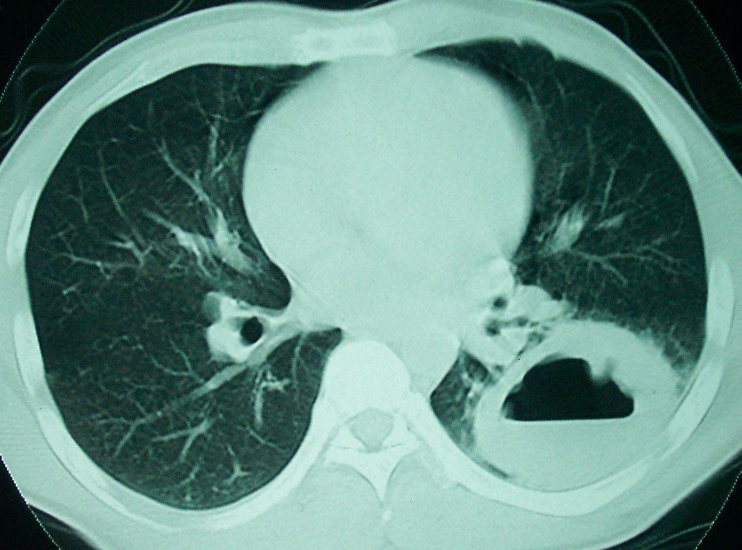

血源性肺脓肿,一般由原发感染灶引起脓毒败血症,在肺部形成小脓肿,病变变化快,容易形成肺气囊,脓气胸,主要与转移瘤鉴别,通过临床病史可分

结合病史考虑血源性肺脓肿,与转移瘤鉴别

结合临床发热,咳痰考虑为血源性肺脓肿,不过双肺结节又在肺的边缘,还是小心一点,抗炎后复查吧

血源性肺脓肿,一般由原发感染灶引起脓毒败血症,在肺部形成小脓肿,病变变化快,容易形成肺气囊,脓气胸,主要与转移瘤鉴别,继续抗炎治疗复查。